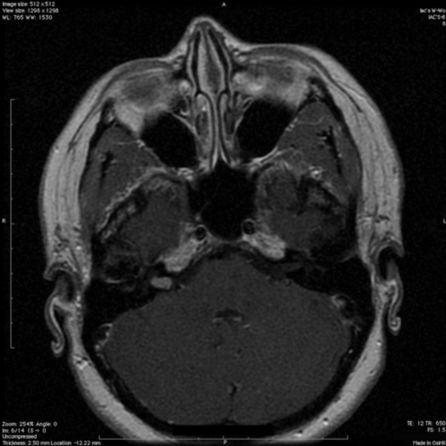

6.多毛症合并颅内黑色素瘤1例报道

Hypertrichosis lanuginosa acquisita associated with intracranial melanoma: case illustration.

PMID: 28707995 DOI: 10.3171/2017.2.JNS162723.

本文首次在文献中报道1例多毛症(Hypertrichosis lanuginosa acquisita, HTLA)合并颅内黑色素瘤病例,临床表现、影像图片、术中所见如下图所示。

【周川】